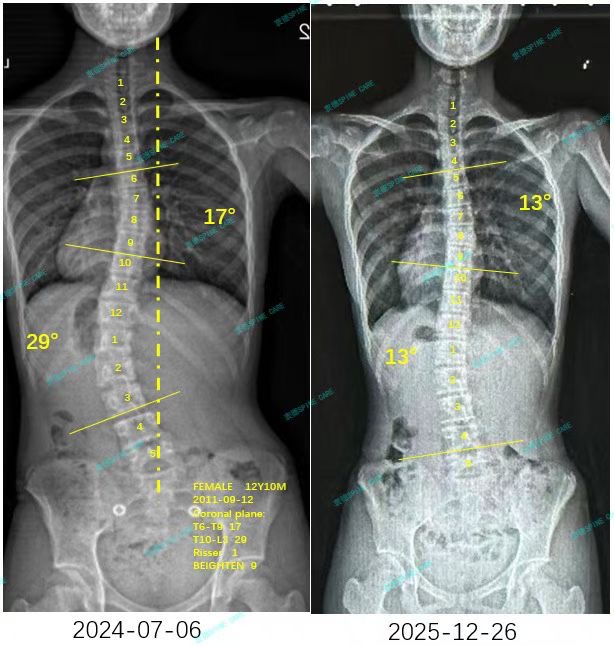

我是涵涵,29度降至13度,体态改善明显~

案例主人:涵涵 发现侧弯年龄:13岁 侧弯情况:Cobb角度29度

期间杨博士每周都会评估我的体态,及时调整治疗方案,这次复查我的腰弯从29度下降到了13度,胸弯也从17度降到了13度,效果非常好,特别感谢杨博士和所有康复老师!

During this period, Dr. Yang evaluated my posture every week and adjusted the treatment plan in time. This time, my waist bend dropped from 29 degrees to 13 degrees, and my chest bend also dropped from 17 degrees to 13 degrees. The effect was very good. Special thanks to Dr. Yang and all rehabilitation teachers!